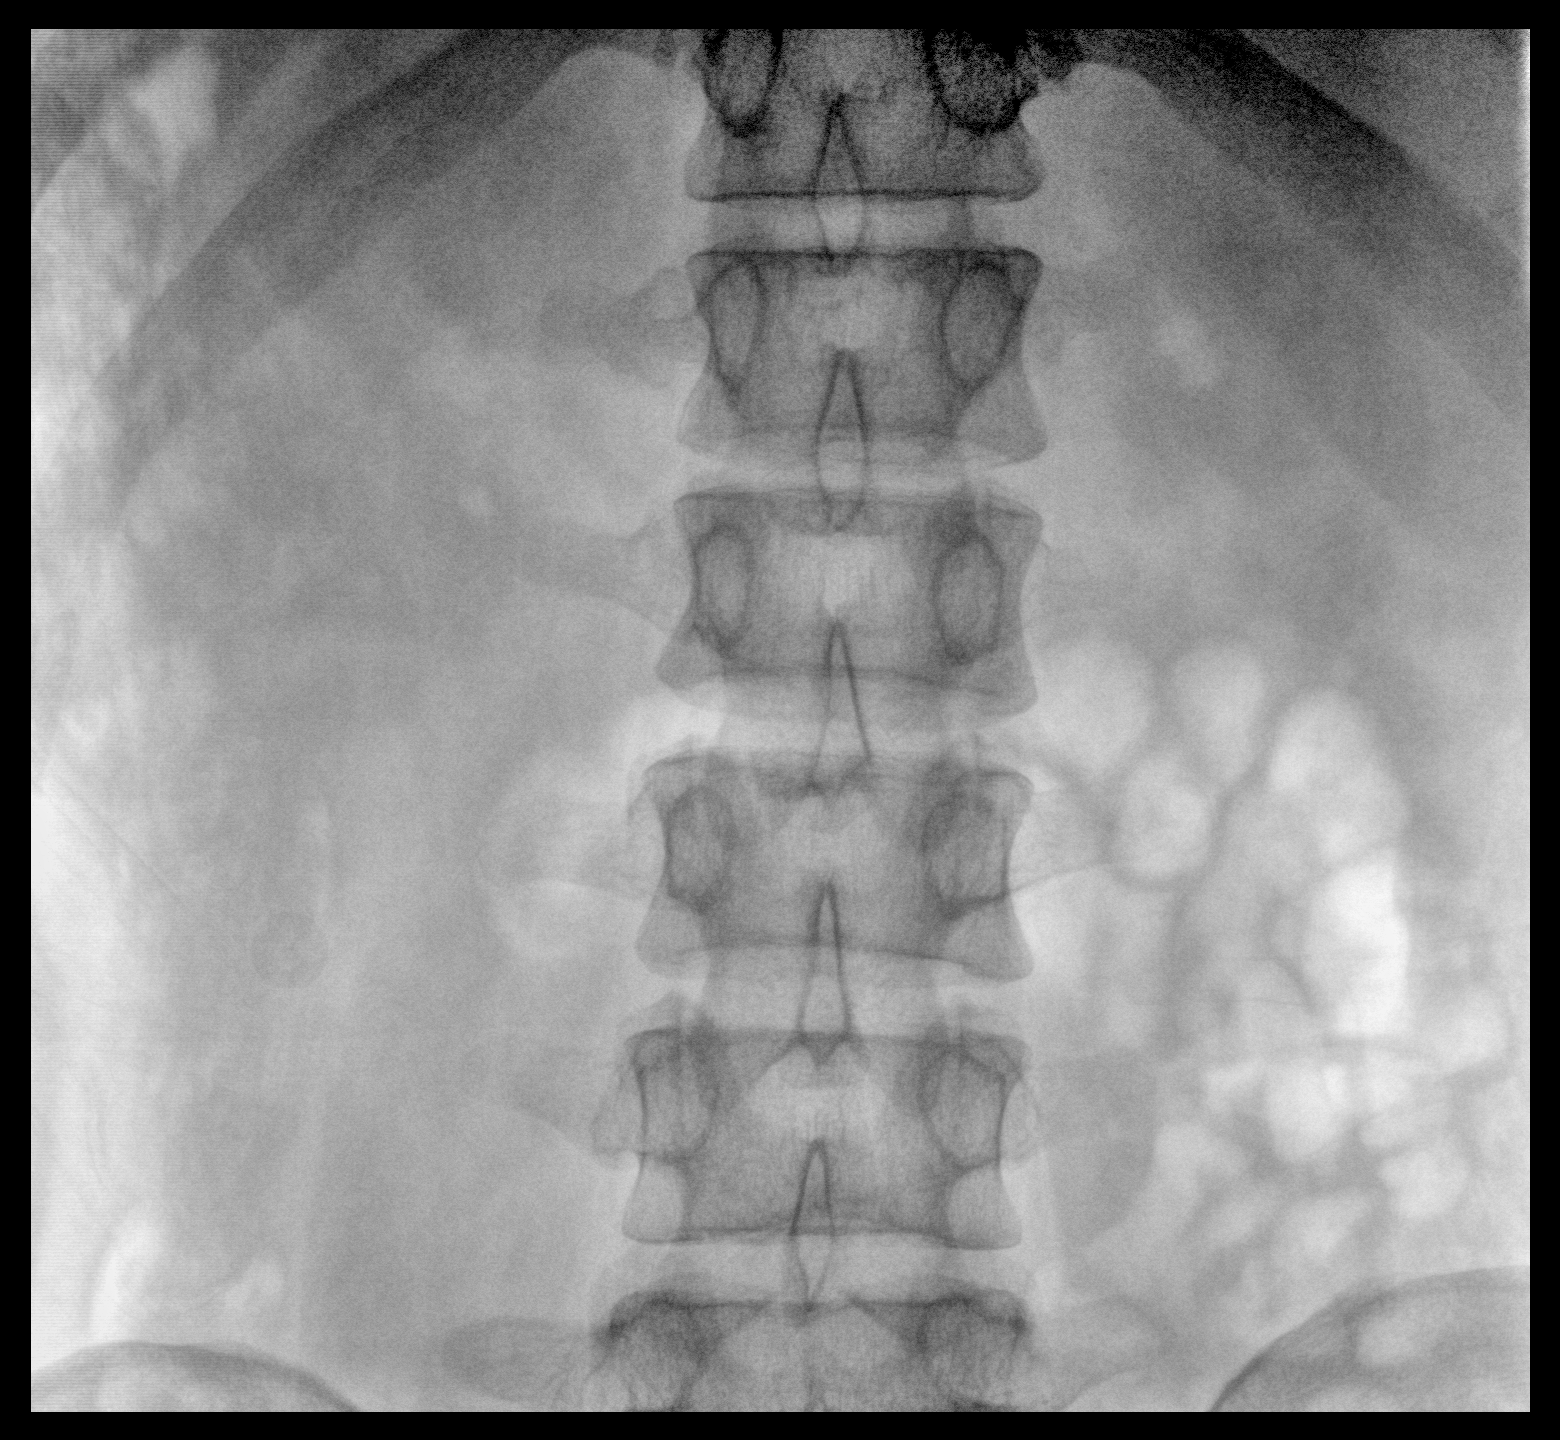

临床适用科室:骨科、普通外科、矫形外科、创伤外科、泌尿外科、脊柱外科、疼痛外科、消化科、妇科等科室。

大尺寸动态平板探测器,高DQE、低噪声、图像清晰。采用多分辨率图像增强处理技术,不同部位不同图像处理算法,满足客户多样化的需求。

采用智能变频脉冲透视技术,优化图像质量的同时降低辐射剂量,呵护医患健康